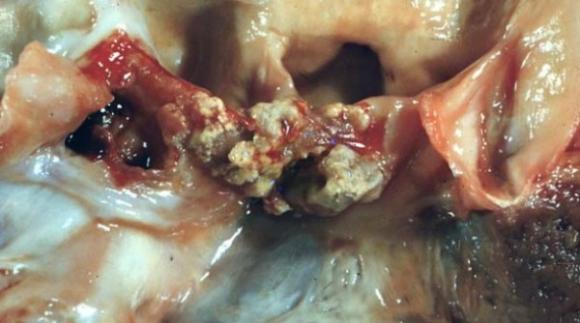

Científicos de la UBA diseñaron una técnica para diagnosticar el origen de la endocarditis infecciosa. Esta enfermedad es producida por microorganismos que ingresan a la sangre durante intervenciones quirúrgicas y se depositan en las válvulas cardíacas. Si no se la trata a tiempo, puede ocasionar serias complicaciones.

Estas son algunas consecuencias severas en las que puede desencadenar una endocarditis infecciosa, enfermedad del corazón producida por microbios que ingresan al torrente sanguíneo a través de las mucosas, frecuentemente durante procedimientos quirúrgicos, incluidos los odontológicos. El tratamiento temprano adecuado es fundamental para disminuir la morbimortalidad, para lo cual es necesario conocer los agentes causantes de la afección. He aquí el problema.

El método microbiológico convencional utilizado para el diagnóstico es el hemocultivo, que multiplica los microorganismos para poder identificarlos. En un medio líquido, se realiza un cultivo de la sangre del paciente afectado y otro de su válvula cardíaca. Sin embargo, este último suele resultar negativo porque, antes de llegar al punto de tener que extraerle la válvula a la persona, el médico intenta curarla con antibióticos. Por otro lado, existen bacterias posibles causantes de la enfermedad que no son capaces de crecer en los medios de cultivo.

Para superar estas barreras, científicos del Instituto de Investigaciones en Microbiología y Parasitología Médica (IMPaM-UBA / CONICET) y del Hospital de Clínicas José de San Martín (UBA), están desarrollando un nuevo método. La técnica consiste en extraer el ADN de las posibles bacterias causantes de la endocarditis directamente de la válvula cardíaca.